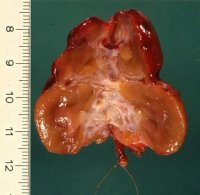

Makroskopisch findet sich infolge der eingezogenen Narben eine höckrige Oberfläche der Nieren, deren Gewicht deutlich verringert ist. Es kann sich um total geschrumpfte Organe mit bindegewebiger Umwandlung von Rinde und Mark bzw. großbuckeligen Formen mit einzelnen groben Einziehungen und Verschmälerung des Parenchyms handeln (s. Abbildung 2, 3b). Auf der Schnittfläche ist die Mark-Rinden-Zone oft nicht abgrenzbar. Die Narben verlaufen keilförmig, teilweise bis ins Nierenbecken (s. Abbildung 4b). Das Hilusfettgewebe ist vermehrt ("Vakatwucherung") (s. Abbildung 18)

Die Abbildungen zeigen pyelonephritische Schrumpfnieren, die im jüngeren Erwachsenenalter wegen Hypertonus bzw. rezidivierenden Harnwegsinfekten auffielen, aber mit Wahrscheinlichkeit im Kindesalter entstanden sind (Abbildung 2,3,4,18).